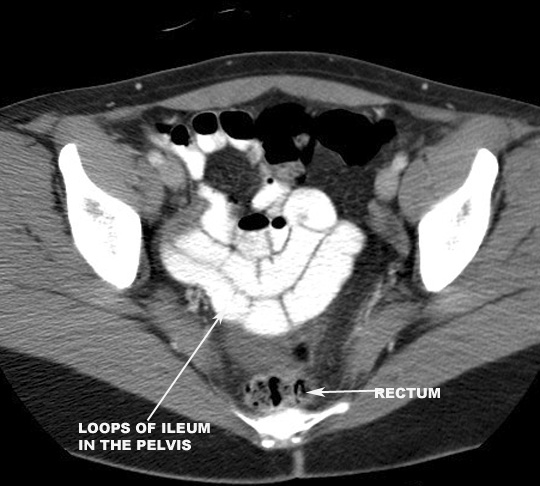

Where is the ileum usually located? Click the image for labeling.